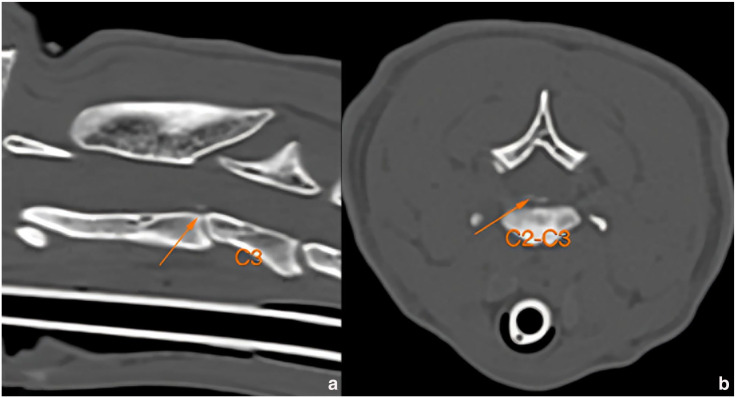

病例摘要:一只两岁大的绝育雌性短毛猫在一次交通事故后出现四肢瘫痪。脊柱放射线检查显示,C2-C3 颈椎脱位,CT 扫描证实了这一点。通过腹侧入路使用螺钉和聚甲基丙烯酸甲酯(PMMA)进行了手术稳定。术后 CT 扫描显示,植入物的位置正确,半脱位得到了很好的缓解。术后,猫咪的神经功能迅速恢复正常:外伤引起的颈椎半脱位在猫科动物中并不常见,但应在鉴别诊断中予以考虑。本报告描述了使用螺钉和 PMMA 对猫的 C2-C3 颈椎脱位进行手术治疗的情况。这是首例通过手术治疗猫颈椎轴下脱位的病例报告。

Case summary: A 2-year-old spayed female domestic shorthair cat presented with tetraparesis after being involved in a road traffic accident. Survey spine radiographs revealed a C2-C3 cervical subluxation, which was confirmed by a CT scan. Surgical stabilisation was performed using screws and polymethyl methacrylate (PMMA) via a ventral approach. A postoperative CT scan demonstrated correct implant positioning and good reduction of the subluxation. After surgery, the cat rapidly recovered to a neurologically normal status.